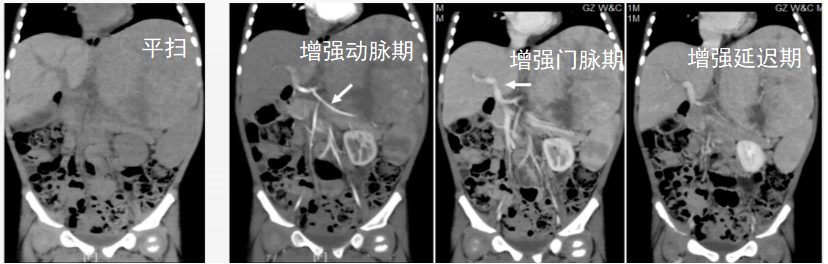

如下图,通过增强扫描,医生能清晰判断肿瘤与周围重要血管的关系,这对于制定安全的手术方案至关重要。

CT增强扫描示肝巨大占位性病变与重要血管(箭头)的关系